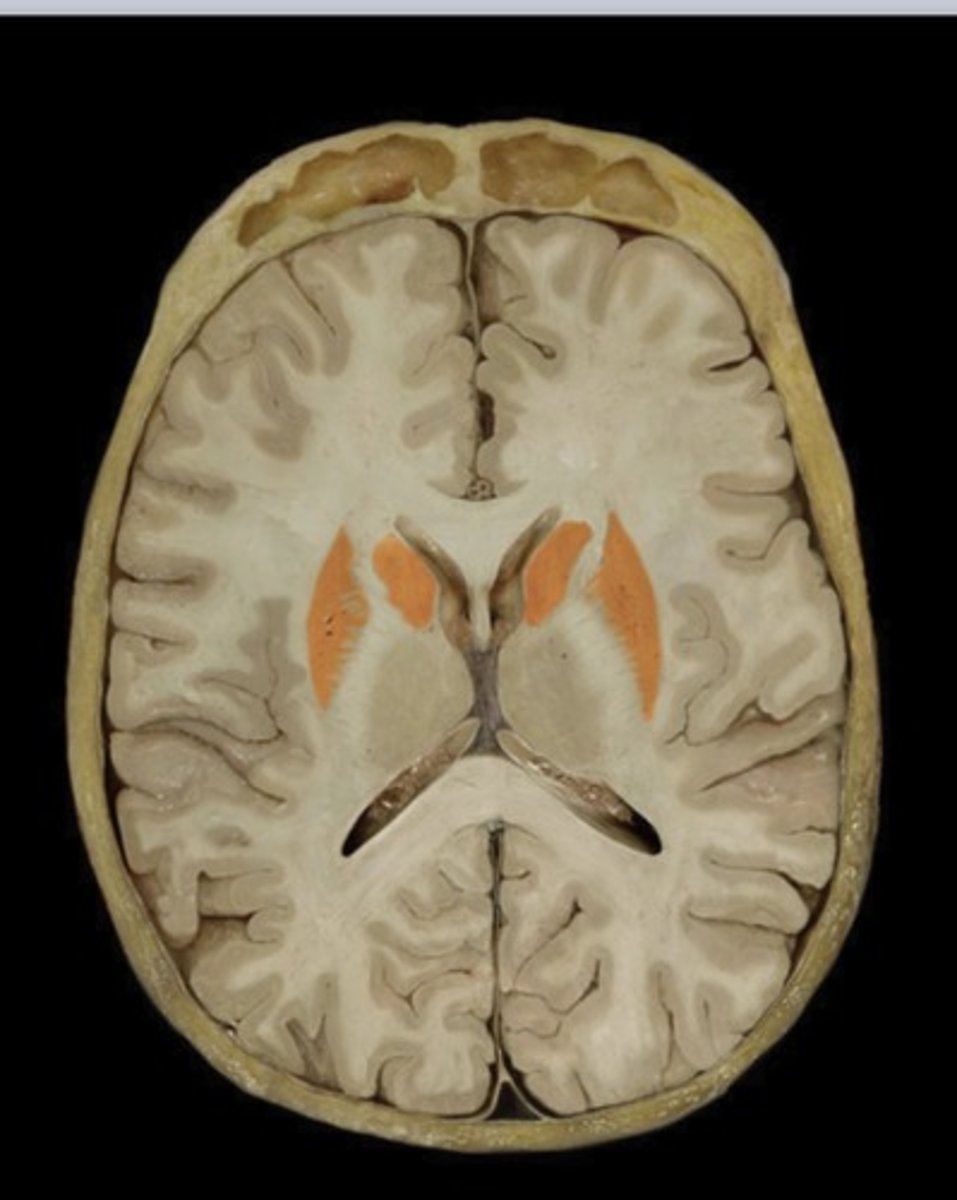

Occipital Lobe (transverse section)

Name this structure

Basal Nuclei

Name this structure

Posterior Horn of the lateral ventricle

Name this structure

Splenium of corpus callosum

Name this structure

Temporal Lobe (transverse section)

Name this structure

Thalamus (transverse section)

Name this structure